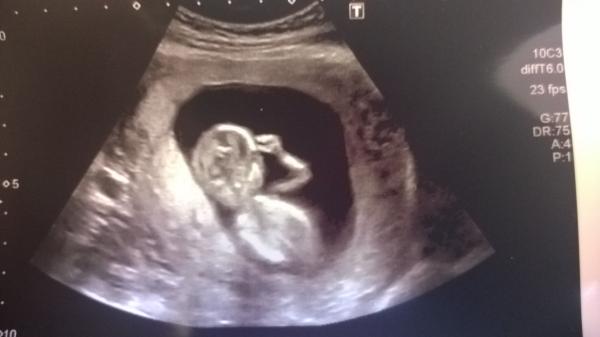

November 2014- thread 4- 12 week scans and blooming in the second trimester!

Here is to more positive 12 week scans and enjoying our second trimesters, all feeling more human hopefully!

Good luck to everyone else with scans this week. Here is to more wriggly, happy babies!

Got my scan in 3 hours! Hospital is about 16 miles away so setting off early to beat the rush hour traffic, nervous now!

Scan in about three hours for me too!

Yay to another week filled with positive scan news. I hope you all enjoy seeing your little ones. I look forward to your updates and pics

I am! it doesn't have caffeine in it but it is chock full of glucose. it was the only thing I could find in the car to chug beforehand and I knew I had to have a full bladder. Highly recommended. The minigoose was doing backflips.

In my scan Bean was chilling out with its arms up by its head and its legs kicking like it was swimming, but not much movement apart from that. Will try the Lucozade next time!